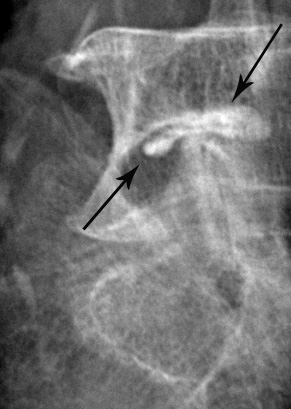

Radiographie de l'épaule. L'épaule a 2 articulations : l'articulation acromio-claviculaire (flèche pleine) et l'articulation omo-humérale (flèche creuse).

Infiltration de l'articulation omo-humérale (épaule).

Après ponction directe de l'articulation, il est injecté du produit de contraste afin de s'assurer de la position intra-articulaire de l'aiguille avant d'injecter l'anti-inflammatoire.